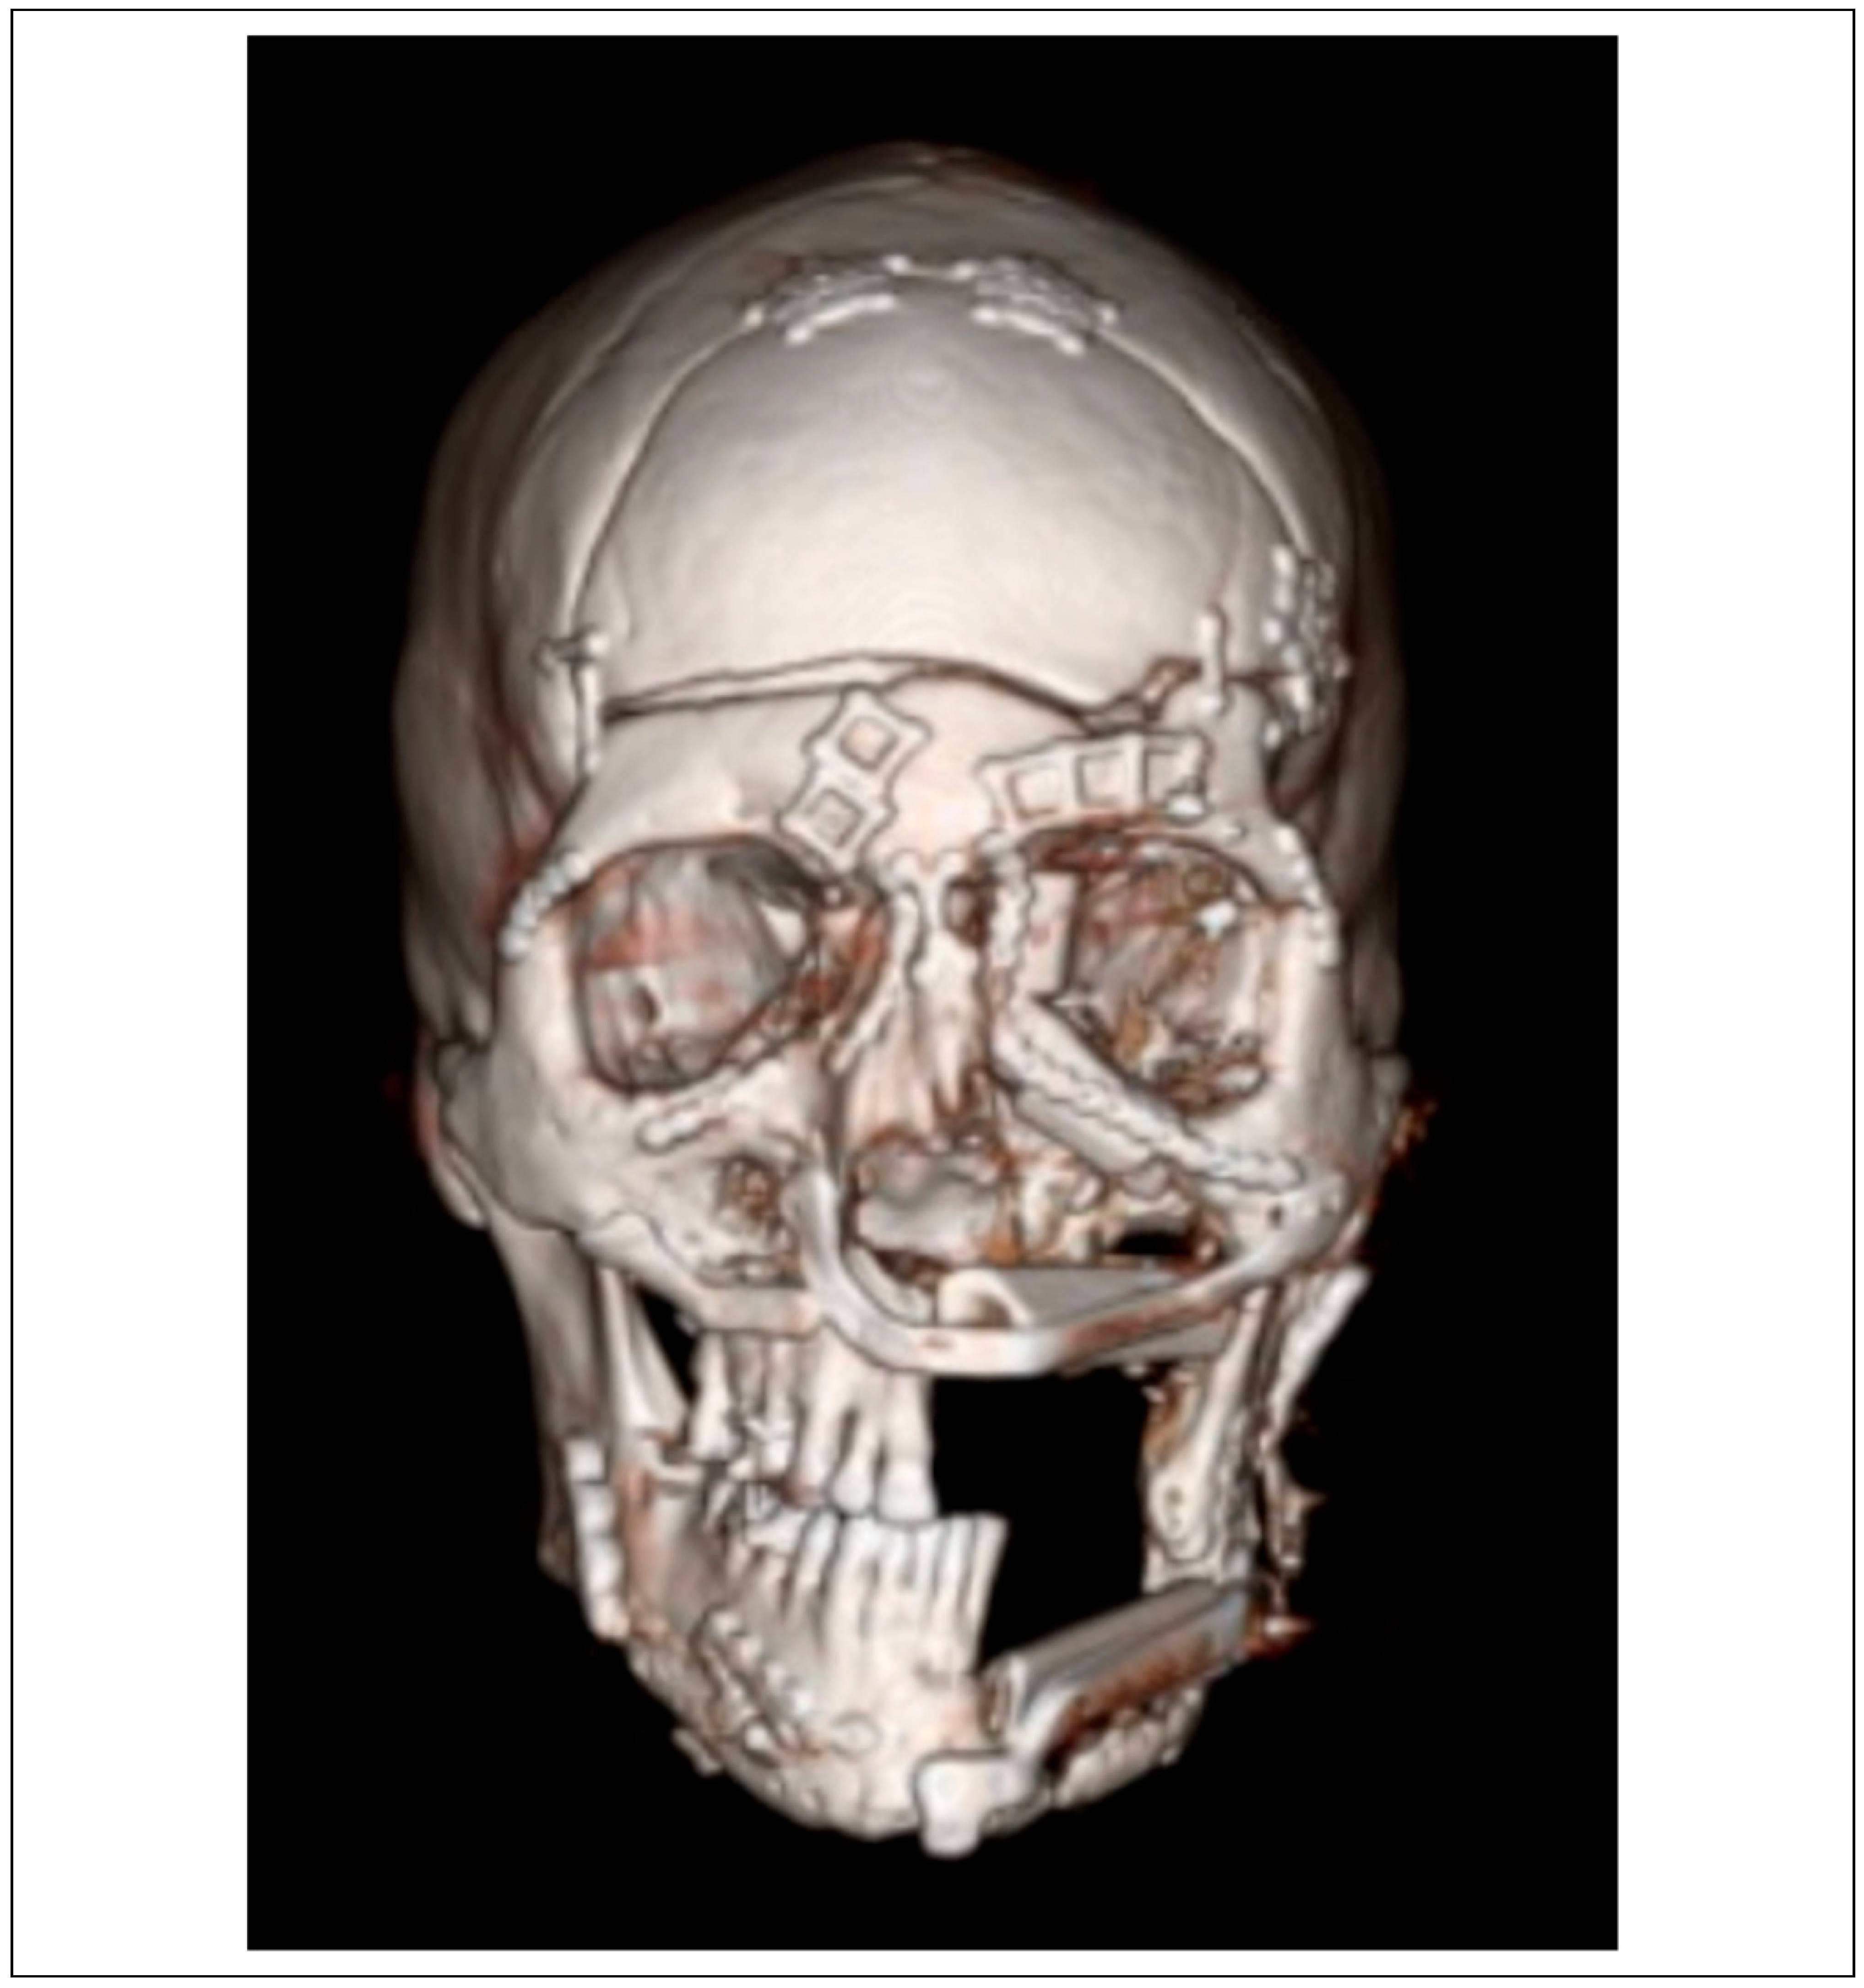

Case Series

Case Presentations